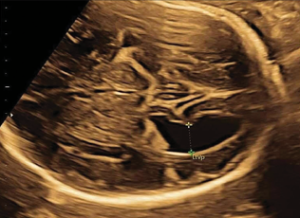

Giãn não thất thai nhi là gì? Định nghĩa: Giãn não thất là tình trạng [...]

GIÃN NÃO THẤT LÀ GÌ: NHỮNG ĐIỀU CẦN BIẾT ĐỂ CHA MẸ KHÔNG QUÁ LO LẮNG

Khi đi siêu âm thai định kỳ, nhiều phụ huynh không khỏi lo lắng khi [...]